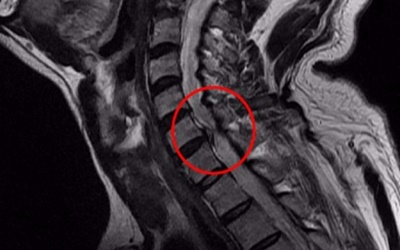

이를 의학계에서는 경추 추간판 탈출증이라고 한다고 하고요. 경추와 뼈들 사이에 존재하고 있는 물렁한 뼈조직이 있으며, 이를 디스크라고 하더라고요. 문제가 되는 것은 이 디스크가 외부로 탈출해서 신경을 압박하면서 통증이 시작되어요.